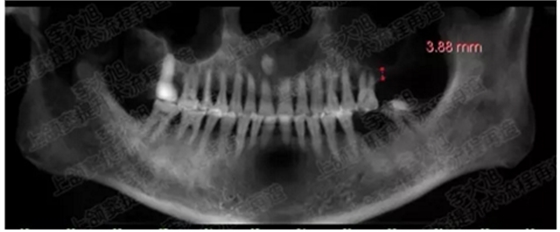

病例一

上頜竇多分隔3mm

05.png

提升8mm